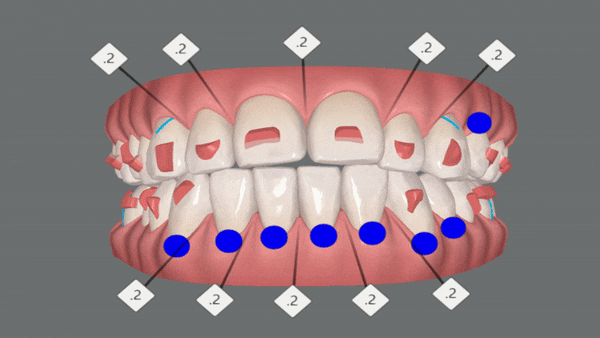

클린체크를 통해 어떻게 변화했는지 같이 확인해보실게요~!

인비절라인은 치아이동 시뮬레이션을 클린체크를 통해 확인 해 볼 수 있는것이 인비절라인 장점중의 하나 입니다.

클린체크란?

환자의 초기 임상 상태부터 치료를 마친 최종 교합상태까지 모든 치료 단계를 시뮬레이션하고, 치아의 미세한 움직임까지 3D 컨트롤 할 수 있는 디지털 플랫폼 입니다. -출처: 인비절라인-

첫번째 클린체크

1st Clincheck

총 29개의 인비절라인 장치로 클린체크대로 마무리가 되었습니다.

오른쪽 클린체크를 보시면 어금니들이 뒤로 이동하면서 동시에 함입이 됩니다.

인비절라인은 특수 강화 플라스틱 장치로 치아를 안쪽 , 바깥쪽에서 잡아주기 때문에 어금니 함입과 동시에 치아 배열이 가능합니다. 불필요한 치아이동이 없기때문에 기간이 단축 될 수 있는 장점이 있습니다.